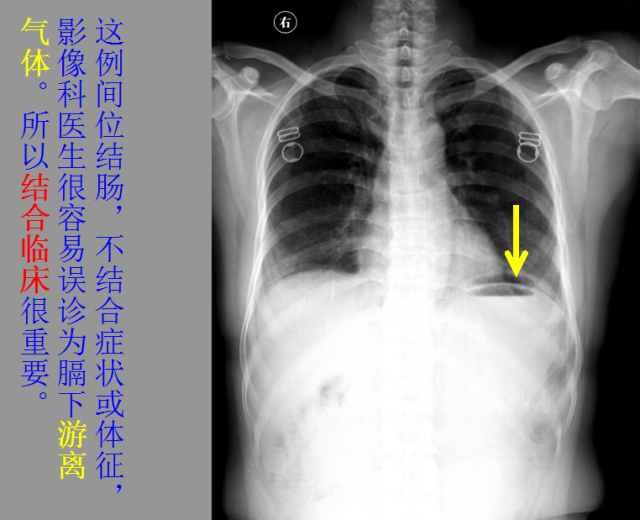

急胸症篇

急腹症篇